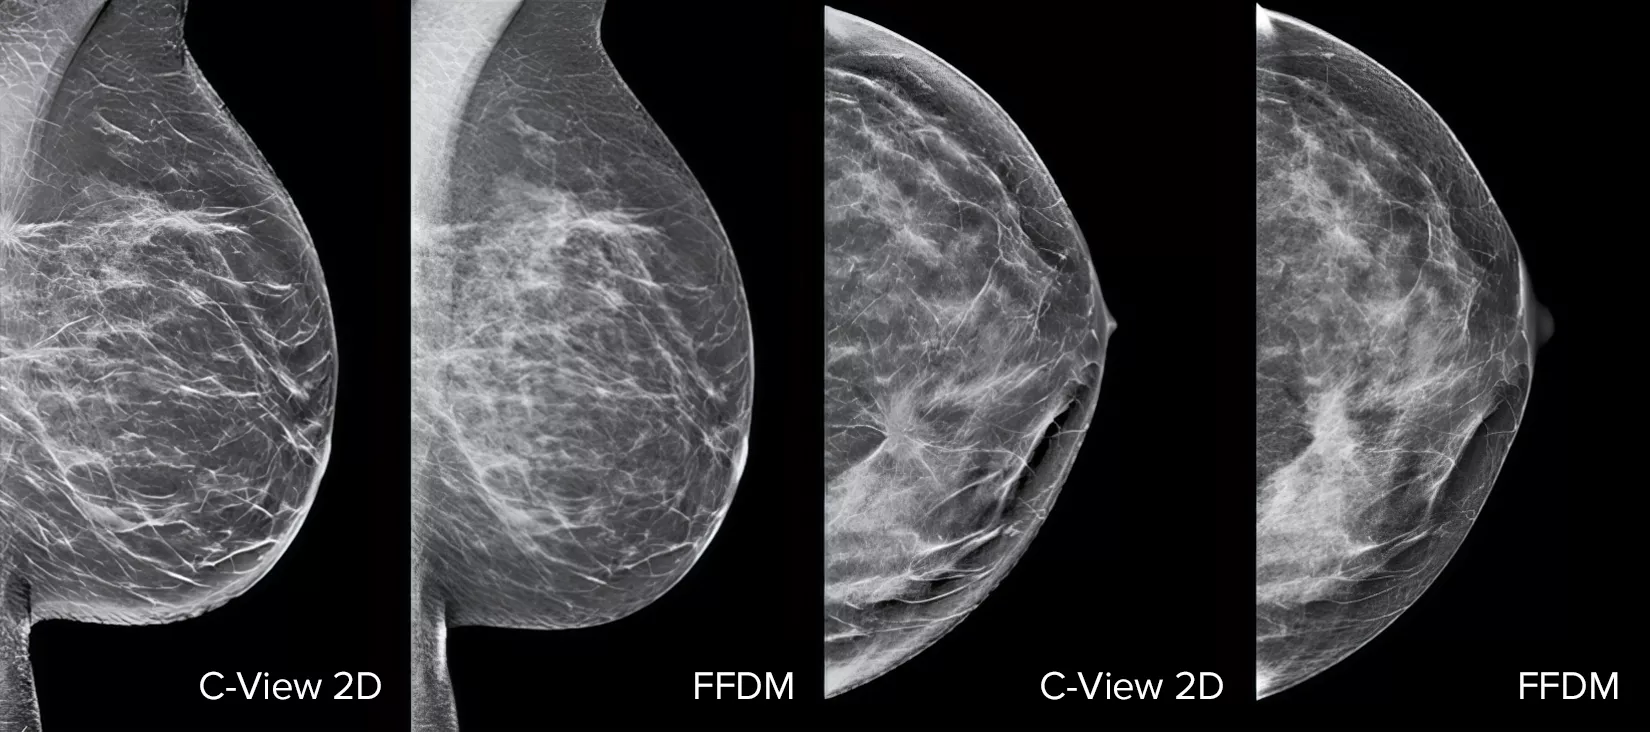

Höj prestandan för bröstcancerscreening1–4 med C-View-programvaran och omedelbart genererade syntetiserade 2D-bilder. Den förbättrar inte bara detaljerna och påskyndar analysen, utan minskar även stråldosnivåerna för patienterna. C-View 2D-bilder är kliniskt bevisade3, 5 och FDA-godkända för att diagnostiskt ersätta FFDM-bilderna i en screeningundersökning med tomosyntes.

Strukturella distorsioner, expansiva lesioner och ljusa fläckar som vanligtvis förekommer i mikroförkalkningar är synligare på en C-View 2D-bild än på traditionella FFDM 2D-bilder eller tomosyntessnitt.4, 6–9

Beviset finns i detaljerna

C-View 2D-bilder är kliniskt bevisade3, 5 och FDA-godkända för att diagnostiskt ersätta FFDM-bilderna i en screeningundersökning med tomosyntes. Bilderna är även en navigeringshjälp vid granskning av tomosyntessnitt. Publicerade studier påvisar att 3D-mammografiundersökning vid låg dos hittar invasiv cancer tidigare, samtidigt som den även minskar frekvensen av falskt positiva återkallade, jämfört med enbart 2D.4, 5, 7